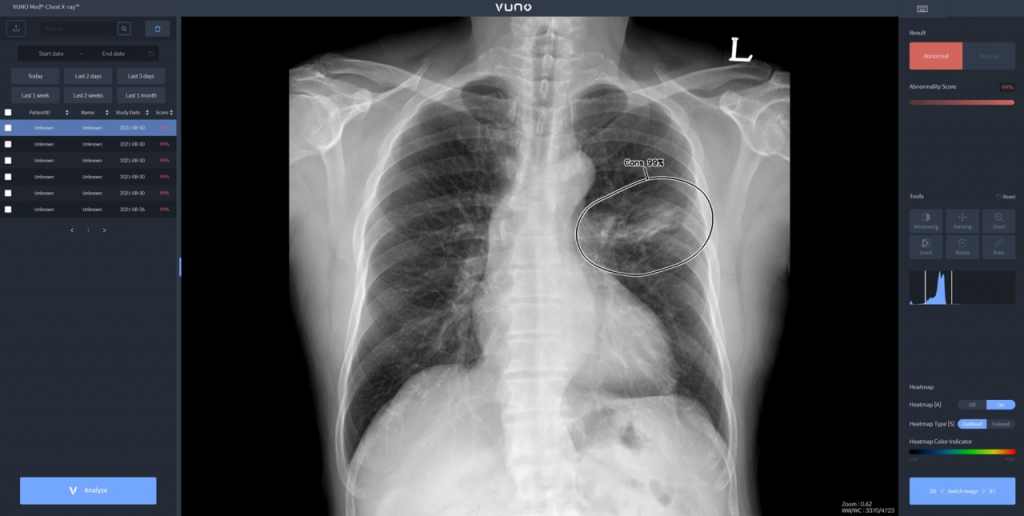

우즈베키스탄 군 병원에 도입된 솔루션은 뷰노의 AI 기반 상지 엑스레이 판독 보조 솔루션 '뷰노메드 익스트리미티 엑스레이'와 이동형 엑스레이 장비에 AI 기반 흉부 엑스레이 판독 보조 솔루션 '뷰노메드 체스트 엑스레이'를 탑재한 패키지 제품이다. 두 제품 모두 뷰노가 과학기술정보통신부 및 정보통신산업진흥원(이하 NIPA)이 추진하는 '군 의료영상 데이터 기반 인공지능 판독 시스템 고도화 및 실증 사업(이하 군 의료 사업)'의 일환으로 개발한 제품이다. 격오지를 중심으로 현장 의료서비스가 가능하도록 설계돼 의료 인프라가 낙후한 지역에서도 진단 편차를 줄이고 의료진의 진단 효율성을 높일 수 있다.

이번에 공급한 뷰노의 '뷰노메드 익스트리미티 엑스레이'는 딥러닝을 기반으로 X선 영상을 분석해 군 장병들의 부상이 잦은 손목, 손, 아래팔, 팔꿈치, 어깨, 위팔뼈 등 6개 부위의 이상 유무와 위치 정보를 제공하는 인공지능 소프트웨어다. 이동형 엑스레이 장비에 '뷰노메드 체스트 엑스레이'를 탑재한 패키지 제품은 별도의 차폐 시설 없이도 다양한 상황에서 환자의 흉부 X선 촬영 후 수 초 이내에 판독 결과를 제공할 수 있다.